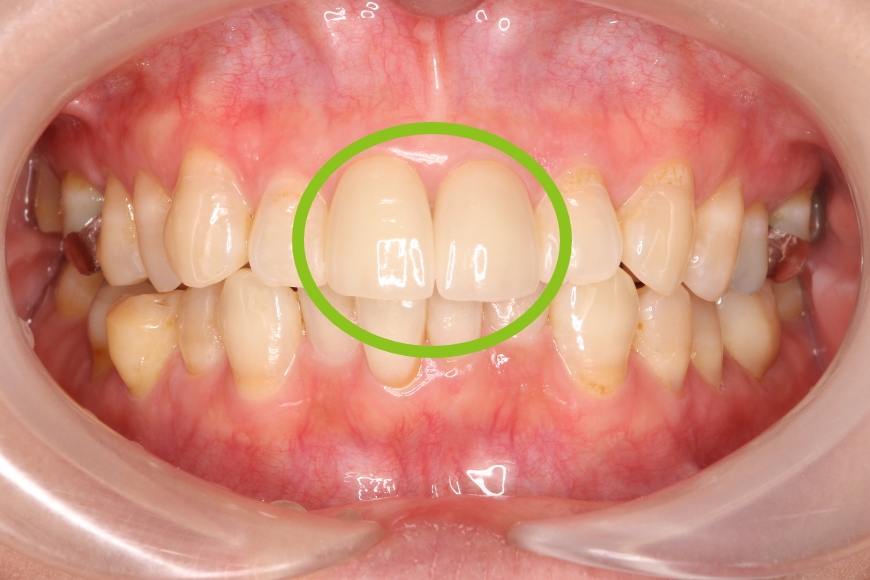

38歳女性 前歯正中離開に対するダイレクトボンディング

治療前

治療後

治療内容 前歯の「すきっ歯」が気になるとのことで来院されました。

矯正治療、セラミック治療、ダイレクトボンディング治療を提案しました。治療期間の短縮と歯質の保存を優先し、ダイレクトボンディングによる治療を選択されました。

ラバーダム防湿下で専用のコンポジットレジンを段階的に充填し形態・色調を再現しました。(歯を削っていません)

治療回数 通院回数:1回

治療費用(総額)

88,000

(1本44,000円×2本分。治療時の金額であり、時期や手法により異なる場合があります。)

副作用・リスク ・歯ぎしりや過度の咬合力により破折する可能性があります。

・時間の経過とともにわずかな着色や摩耗が生じるため、長期的には再調整や再充填が必要になる場合があります。